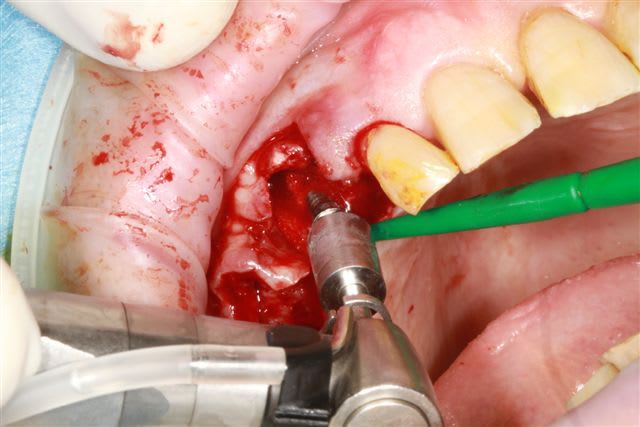

modelage zone 13,finitions, mise en place du bloc osseux, qui sera soigneusement impacté (pas de vis) prélèvement d'un petit bloc triangulaire pour finir la fermeture, éponges de gelatemp, sutures.